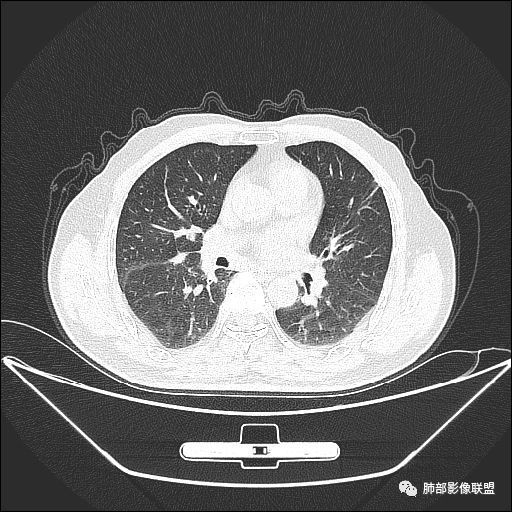

入院CT

老年男性,亚急性病程,咳嗽咳痰。右肺中叶团片影,外朝内分布,大部分边界清楚平直,内侧支气管进入,团片影见低密度坏死区,强化明显,延迟强化,血管破坏不明显,符合爬行征5个特点:

1.肺外周生长。

2.外侧部分体积大于内侧。

3.病变最大径与肺的纵轴及水平面任何一条轴线不平行。

4.病变内侧支气管通畅。

5.病变区域肺容积无缩小。

双侧肺门及纵隔淋巴肿大并可见钙化。考虑结核,但部分边缘膨隆,肿瘤待排。

主病灶在中叶,但是左肺舌段叶有条索影,陈旧病变。蓝色箭头支气管受压,是淋巴结肿大

主病灶在中叶,但是还有结节状病变在下叶

这个支气管是走形通畅,但是壁增厚的。比较符合炎症改变

内侧段是通畅但是受压的

外侧段一开始狭窄

但是远端通畅,所以我认为支气管都没有堵塞,不太可能是鳞癌

边缘还有多发小灶

淋巴结肿大,钙化。

但是钙化,密度高,没有融合,平扫没有坏死

病灶明显平直,中央是粘液栓,低密度,分界清楚